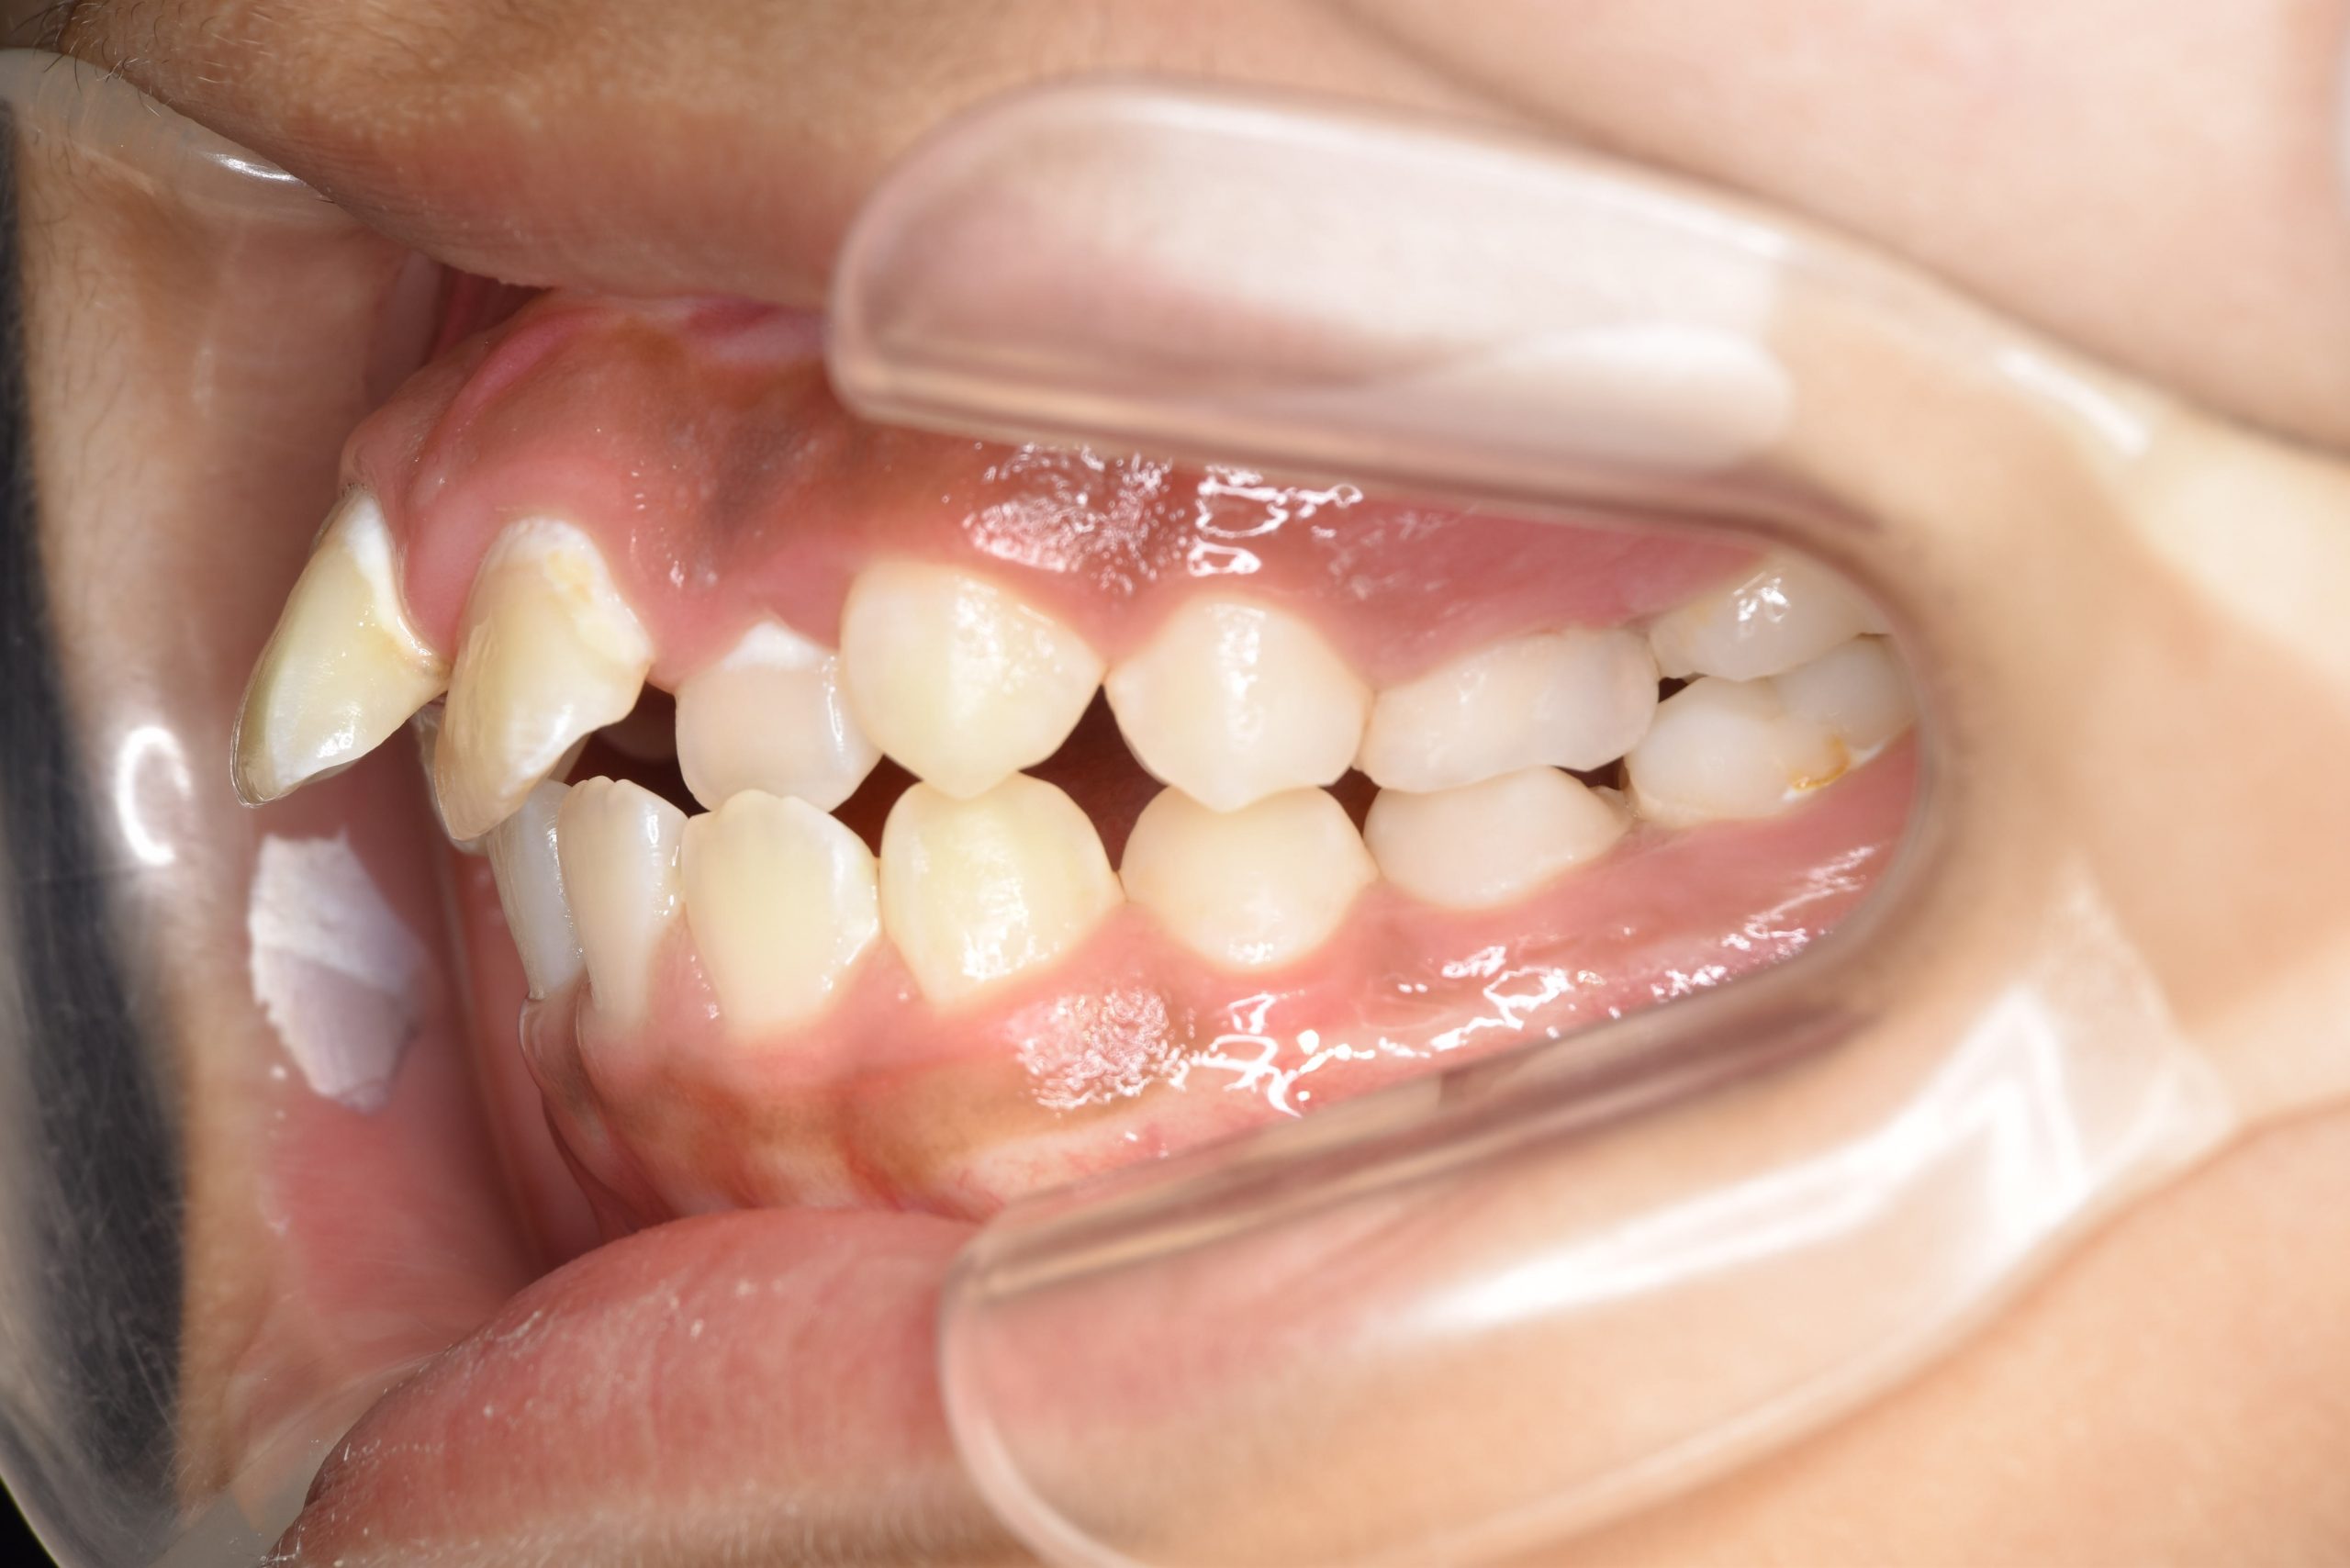

ビフォー

全顎ワイヤー矯正 症例_474

主訴 歯並びがガタガタで前歯が出ている

施術内容 小児矯正1期治療

治癒期間 1年5か月間

費用 1,020,800円(税込)